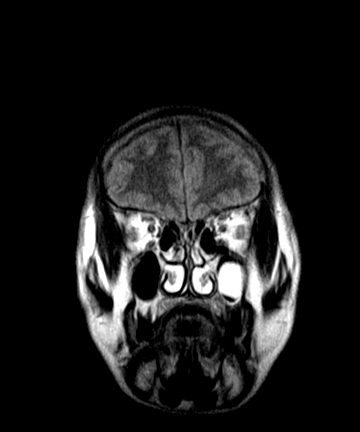

标题: MRI2064:少见病例。男性52,视力下降多年。

考虑第四脑室室管膜瘤并梗阻性脑积水;部分性空蝶鞍;左侧上颌窦粘膜下囊肿。

加左上颌窦囊肿

考虑第四脑室室管膜瘤【血供丰富血管母细胞瘤可能】并梗阻性脑积水;部分性空蝶鞍;左侧上颌窦粘膜下囊肿。

2、左侧上颌窦及蝶窦囊肿。